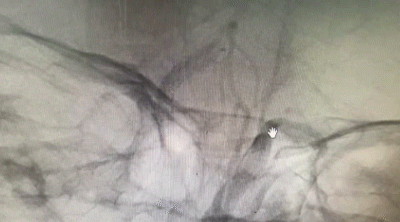

导引导管到位,导丝通过病变。

导丝怎么扩【载药时代 球扩天下】NOVA DES®颅内药物洗脱支架在颅内富穿支区域使用体会二例!_https://www.jmylbn.com_新闻资讯_第31张

支架释放后影像。